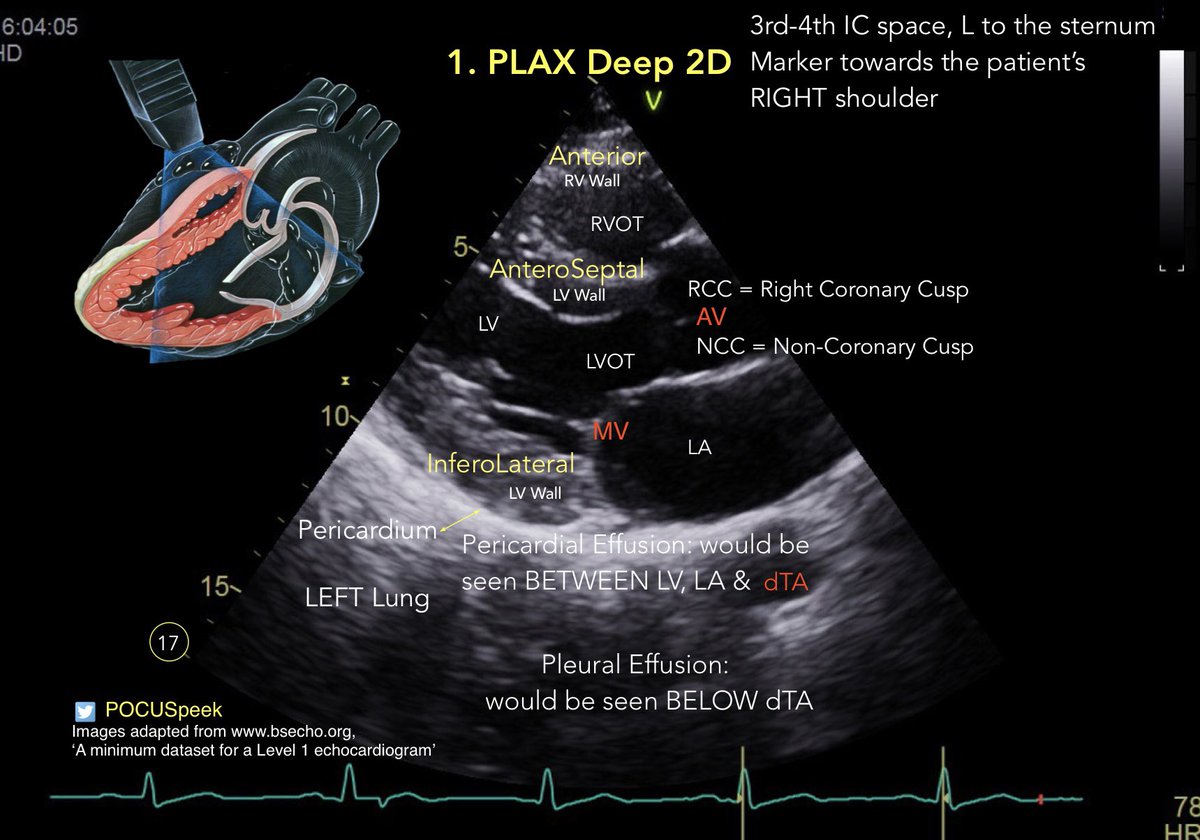

Annotated PLAX views #firstecho #POCUS for @BSEcho level 1 or #FUSICheart @pocusfoamed 🧵 PLAX Deep 2D 👇

🧵 PLAX Deep 2D 👇

Learning #POCUS & Illustrator. #firstecho PLAX Deep 2D view. @pocusfoamed #MedEd #MedTwitter

POCUSpeek's tweet image. Learning #POCUS & Illustrator. #firstecho PLAX Deep 2D view. @pocusfoamed #MedEd #MedTwitter